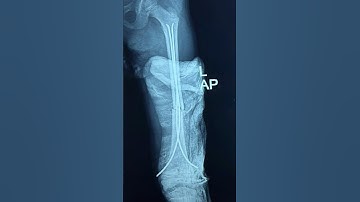

TENS ( titanium elastic nailing) for forearm fracture in children by Dr. Sameer Desai